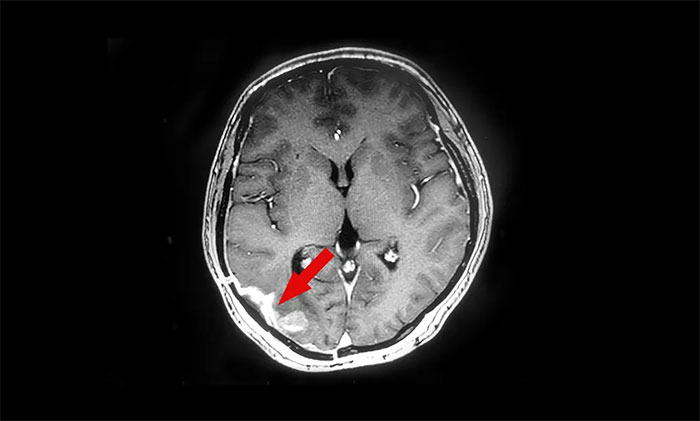

近日,上海藍(lán)十字腦科醫(yī)院腫瘤科(放療)收治了一位腦膠質(zhì)瘤術(shù)后復(fù)發(fā)患者;颊吆(化名),女性,41歲。2021年1月,患者在外院行右側(cè)顳枕部占位切除術(shù),術(shù)后病理示膠質(zhì)母細(xì)胞瘤。行頭部伽瑪?shù)吨委熀,病情趨于穩(wěn)定。

▲治療前

半年后復(fù)查,頭顱MR提示顱內(nèi)腫瘤原位復(fù)發(fā),病灶大小約1.5cm*2.3cm,遂至上海藍(lán)十字腦科醫(yī)院尋求進(jìn)一步治療。陳琦主任團(tuán)隊(duì)為患者完善相關(guān)檢查,并開(kāi)展MDT多學(xué)科會(huì)診評(píng)估,符合伽瑪?shù)吨委熯m應(yīng)癥。治療期間,患者健康狀況平穩(wěn),未出現(xiàn)明顯并發(fā)癥。